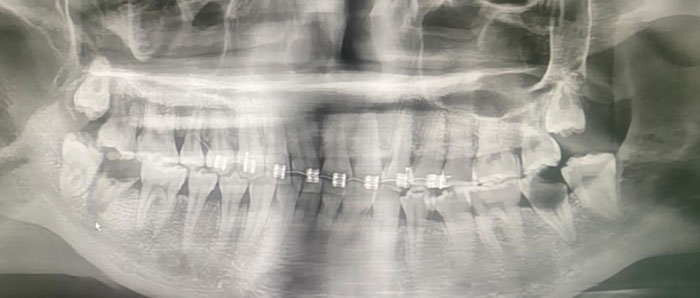

หมอเผยเคส สาววัย 20 ปี จัดฟันแฟชั่นในกรุงเทพฯ เพียง 6 เดือน อาการทรุดจนเชื้อลุกลามเข้ากระแสเลือด สุดท้ายต้องผ่าตัดเปลี่ยนลิ้นหัวใจ แม้อายุยังน้อย

โพสต์ดังกล่าว ระบุว่า Line เด้งจาก Somporn Keawnim หัวหน้าตึกหอผู้ป่วยวิกฤตหัวใจ เคสจริงที่หมอเจอ… น้องอายุเพียง 20 ปี เริ่มจากจัดฟันแฟชั่นในกรุงเทพฯ ฟันผุ มีหนอง เชื้อเข้ากระแสเลือด ตรวจพบเชื้อ Streptococcus gordonii กลายเป็นเยื่อบุหัวใจติดเชื้อ (Infective Endocarditis) สุดท้ายลิ้นหัวใจรั่ว ต้องผ่าตัดเปลี่ยนลิ้นหัวใจ ทั้งที่ยังอายุน้อยมาก

จัดฟันแฟชั่นทำมาจาก กทม. เมื่อประมาณ 6 เดือนที่แล้ว เริ่มมีอาการไอ หายใจไม่ค่อยสะดวก จึงโทร. หาแม่ แม่เลยพามารักษาที่น่าน น้องอายุเพียง 20 ปี แม่ให้ลาออกจากงานเพื่อมารักษาตัวให้หายก่อน

จัดฟันแฟชั่นทำพร้อมกันเป็นกลุ่มกับเพื่อนอีกหลายคน โอย เพื่อนรู้หรือยัง

แต่ชีวิตอีกช่วงหนึ่งกลับต้องใช้ลิ้นหัวใจเทียมไปตลอด คิดให้ดี ๆ

กับการจัดฟันที่ไม่ได้มาตรฐานนะคะ ตระหนัก และตระหนกกันด้วยนะคะ